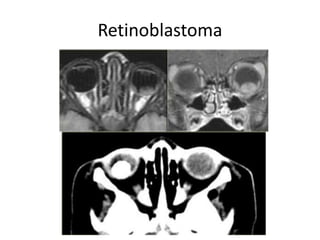

Retinoblastoma

• Common tumor in the first year of life

• Child < 3 years of age (98%)

• Other presentations: leukokoria, strabismus,

decreased visual acuity, family hx, eye pain,

proptosis

• Believed to arise from neuroectodermal cells

• 75% unilateral; 25% bilateral

• All bilateral cases are hereditary (AD) >>

deficient tumor suppression gene on

chromosome 13

• 90% calcified

• Techniques

– CT is prefered to detect calcification

– MR serves an adjunctive role

• Findings:

– CT: an intraocular mass with calcification

in a child<3 yr -> should consider retinoblastoma

– Extraocular spreading along the optic nerve

– Together with pinealoma

-> trilateral retinoblastoma